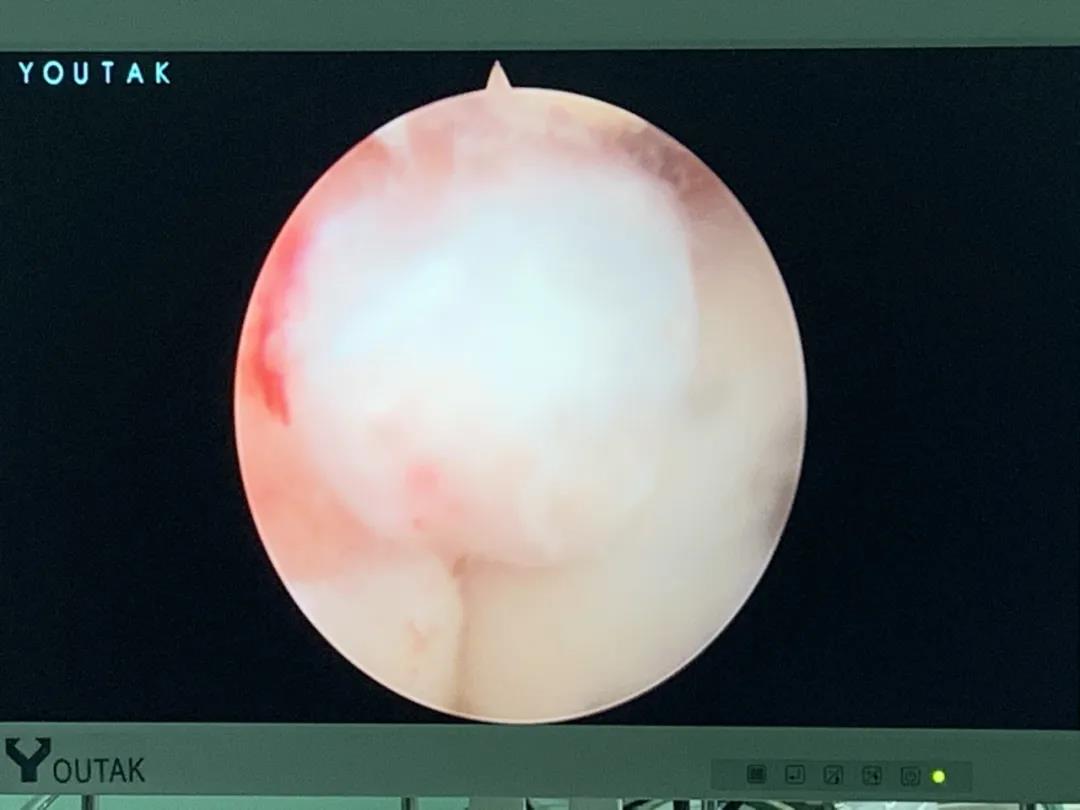

骨二科開展肩關節(jié)鏡下肩袖損傷修補術,采用雙排縫線橋技術,更好的促進肩袖撕裂的愈合,同時開展肩關節(jié)鏡下凍結肩(肩周炎)的松解治療,早期恢復肩關節(jié)的功能,減輕疼痛,同時開展肩關節(jié)Bankart損傷SLAP損傷及肩關節(jié)不穩(wěn)的關節(jié)鏡治療。

肩關節(jié)鏡下肩袖損傷修補術